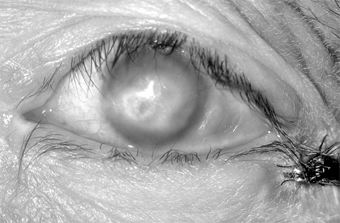

Conjunctival scarring is a frequent complication of trachoma and can destroy the ductules of the accessory lacrimal glands and obliterate the orifices of the lacrimal gland. These effects may drastically reduce the aqueous component of the precorneal tear film, and the film's mucous components may be reduced by loss of goblet cells. The scars may also cause distortion of the upper lid with inward deviation of individual lashes (trichiasis) or of the whole lid margin (entropion), so that the lashes constantly abrade the cornea. This often leads to corneal ulceration, bacterial corneal infections, and corneal scarring (Figure 5-2).

Figure 5-2

Figure 5-2: Advanced trachoma following corneal ulceration and scarring. Note the fly on the temporal aspect of the lower lid. The fly is a principal vector for trachoma.

Ptosis, nasolacrimal duct obstruction, and dacryocystitis are other common complications of trachoma.